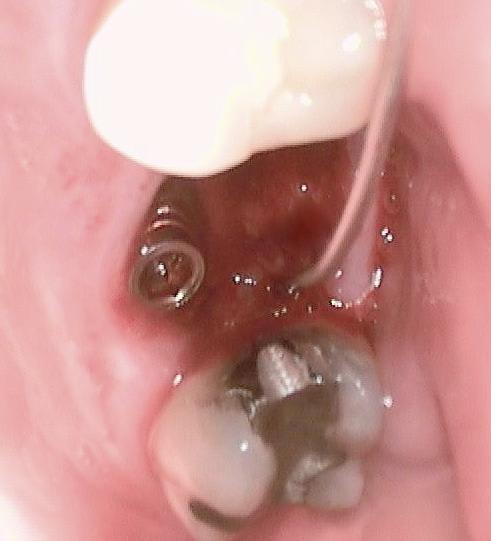

Un patient de 52 ans présente une fracture de racine au site 26.Après division de la racine, extraction de la dent,préparation de la cavité avec un foret conique triangulaire (3 faces,condensation de l´os), puis implantation à 50 Ncm (implant 10mm long, 4,5mm diamètre).Utilisation d´acide hyaluronique pour stimuler la synthèse des ostéoblastes.Pose d´un clip gingival pour préformer la gencive.Après 7 semaines, réalisation d´une empreinte fermée en 5 minutes.Une semaine après, fixation de la couronne définitive ( on observe déjà une ostéointégration).

Je suis surpris du diamètre de l'implant : 4.5 mm, au vu des radios on imagine qu'il est bcp plus petit si l'on considère qu'un molaire sup a un diamètre +/- 10 mm, par rapport à ce diamètre quel est le diamètre de la bague de cicatrisation en teflon ?

Ce qui m'intéresse plus dans ce cas c'est la gestion des tissus mous autour de la bague en post-op : si la chirurgie en mini-invasive, comment tracter les tissus mous en peri-implantaire, la bague me semblant bien étroite pour "remplir" le volume entre le (petit) diamètre de l'implant et le (grand) volume de l'extraction ?

Bonjour je connais bien les techniques du Dr Nedjat pour les pratiquer depuis de nombreuses années. Il me demande de l'aider un peu vu la barriere de la langue pour la réponse aux questions.. On voit sur une radio que passer dans le septum impose de faire un "summers modifié", du type carote osseuse condensée à l'osteotome pour preparer un lit implantaire dans ce cas on peu placer un 8mm en base large et avoir un pilier dans l'axe. OK. Ca n'a pas été son choix car il developpe en Allemagne depuis 15 ans sa technique dite MIMI (voir mon post précédent) qui consiste a fraire une osteotomie avec des expanseurs suite à un forage minimal pour obtenir une stabilité primaire tres élevée la plupart du temps 60/70N..Cette technique est tres répandue en Allemagne, plus de 3000 confreres l'utilisent avec un systeme monobloc ou deux pieces..je vais poster dans les jours qui viennent sufisament d'infos pour que vous puissiez vous faire une idée, j'ai des dizaines de cas iconographiés de A à Z. Dans ce cas oui c'est un 4,5mm, l'implant est posé avec son "shuttle" partie intermédaire porte implant laissé intra muqueux et qui "encaisse" le couple de serrage important de la pose. Dessus est clipsé un "gingiva clips" qui est un conformateur gingival laissé pour la cicatrisation. L'empreinte se fait en laissant Shuttle et gingiva clips. Le shuttle est déposé pour la mise du pilier. Il y a toute une technique ..description à venir et cas cliniques aussi ..A suivre..